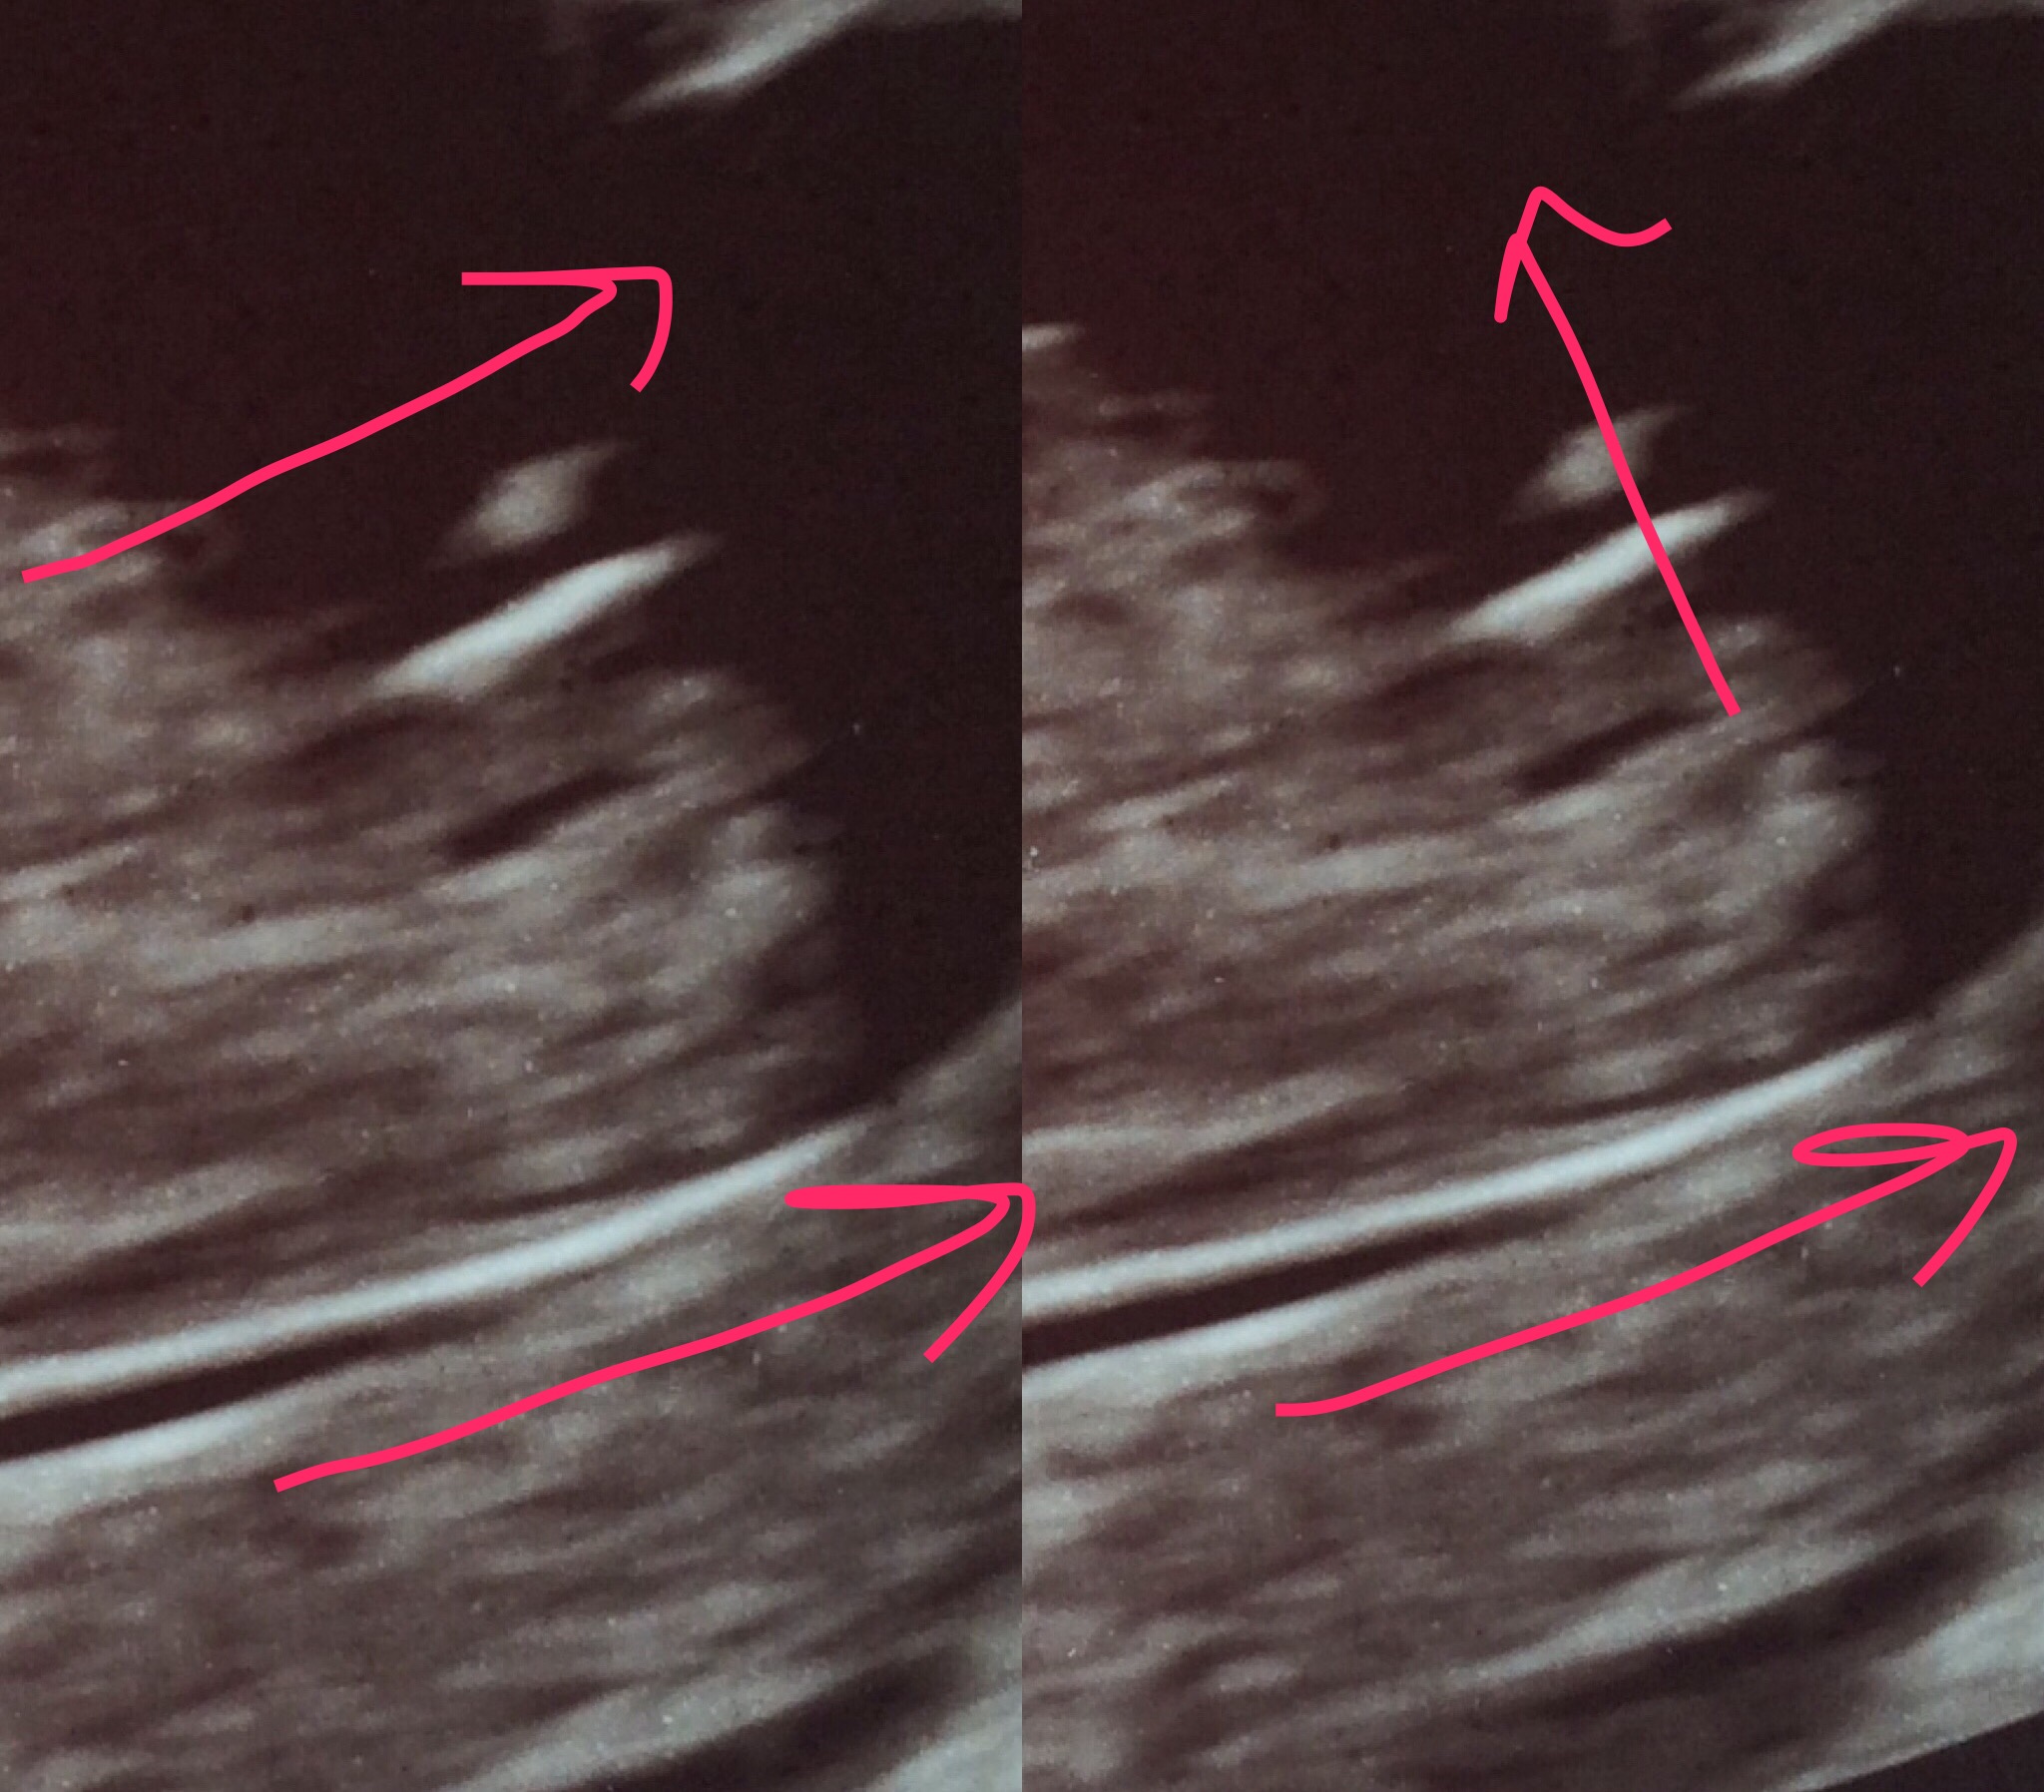

I had my 13 week scan and was told this is very likely a boy. Would y'all agree? If so this will be my third boy and possibly last child. Trying to wrap my brain around never having my girl. I'm also debating if i should splurge for an extra scan to confirm prior to my 22 week scan.